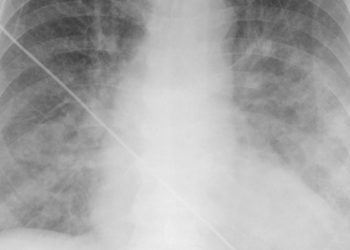

![Spironolactone not beneficial in heart failure with preserved ejection fraction [TOPCAT trial]](https://www.2minutemedicine.com/wp-content/uploads/2014/04/Pulmonaryedema09-350x250.jpg)